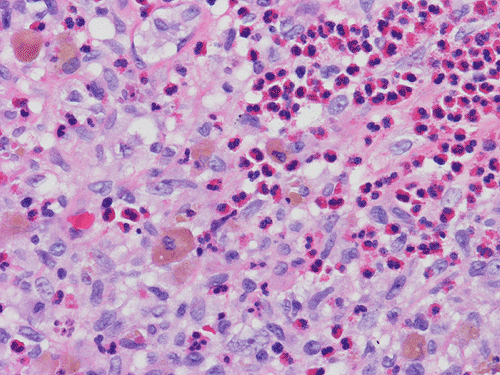

At scanning magnification (Panel A), the lung parenchyma is replaced by some coalescing fibrous nodules. The degree of involvement is variable at different fragments (Panel B and C). In the less affected areas, there are some fibrotic thickening of the septa (Panel C). In some areas, the changes are minimal and the pleural appear to be uninvolved (Panel D and E). In low to medium magnifications, these nodules of fibrosis contains a large number of hemosiderin laden macrophages (Panel F and G) admixed with fibrous tissue. The diagnostic tissue, however, is present in areas with increased cellularity. In these areas, there is a background of cells with a moderate amount of cytoplasm and bland nuclei. Some of these nuclei have kidney shape (arrow in Panel H). In some areas, many of the nuclei have a deep nuclear groove that resemble a coffee bean (arrow in Panel I). In the third type of areas, the nuclear grooving is not distinct (Panel J). Prominent eosinophilic infiltrations are almost always present. Immunohistochemistry on CD1a revealed many positive cells (Panel L). Also present in the specimen are multiple small blood vessels with thickened intima (Panel K). A Movat pentachrome stain demonstrates an internal elastic layer in these vessels and confirms that these are arteries (Panel M and N).

Histopathologic signature of Langerhans cell histiocytosis, namely kidney shaped or coffee bean shaped, bland nuclei associated with eosinophilic infiltration is not difficult to see in most of the cases. The amount of eosinophilic infiltration and the proportion of cells with nuclear grooving, however, can be quite variable but this problem can usually be overcome by a diligent search. Demonstration of CD1a by immuhonistochemistry or Birbeck granules by electron microscopy will confirm the diagnosis.

Pathologically, PLCH can be broadly divided into an early or cellular stage and a late or fibrotic stage. Demonstration of LCs is of critical importance for a correct diagnosis. The morphology of LCs is similar to LCH in other organs. LCs are characterized by a deep nuclear groove which lead to “coffee bean-shaped” or “kidney-shaped” nuclei. In most cases, the level of atypia and pleomorphism is low. A moderate amount of amphophilic to weakly eosinophilic cytoplasm is present. The cytoplasmic membrane is indistinct. Eosinophils and chronic inflammatory cells, varying from scant to abundant, are present. Except for a scant frankly pleomorphic cases, the level of pleomorphism and atypia is minimal to low. Eosinophilic abscesses with central necrosis may be present. Immunohistochemically, LCs are similar to their normal counter parts and are positive for CD1a and S100. At the ultrastructural level, Birbeck granules can be demonstrated. For most cases, the diagnosis can be established by histopathologic criteria but these additional features help to confirm the diagnosis.